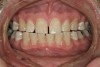

The teeth themselves often can be full of diagnostic information. Is there excessive tooth wear (Figure 7 through Figure 9)? Is there excessive mobility in any teeth? Is there unwanted migration of teeth? Is there a centric relation/maximum intercuspation discrepancy (hit on inclines and slide into full intercuspation) (Figure 3)? If there is a discrepancy, is the deviation in the arc of closure or line of closure? Is the patient able to chew all types of food on both sides without pain? Does the patient feel like their bite is changing or unstable? In addition, are there functional patterns evident by the wear present on the teeth. For instance, horizontal bruxers (Figure 10) often have flat tabletop wear present. Vertical, constricted wear patterns (Figure 11) often have anterior chipping and lingual wear of maxillary anterior teeth.

Figure 3  FUNCTIONAL HARMONY Numerous examples of incline interferences exist in this picture; note the large "hit and slide" evident on tooth No 5.

Figure 3